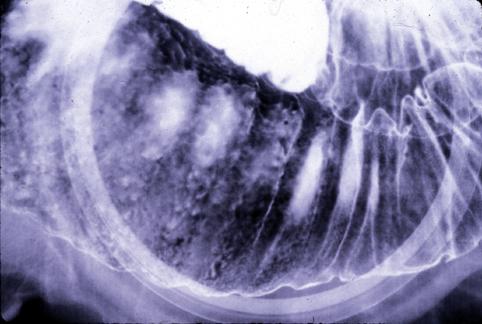

伴有明显肠壁肥厚的原发性B型小肠恶性淋巴瘤(国立癌中心东医院<关口隆三&lgt;和九州癌中心共同做成)

恶性淋巴系肿瘤/恶性淋巴瘤

小肠/空肠

X线

40以上

s(a)